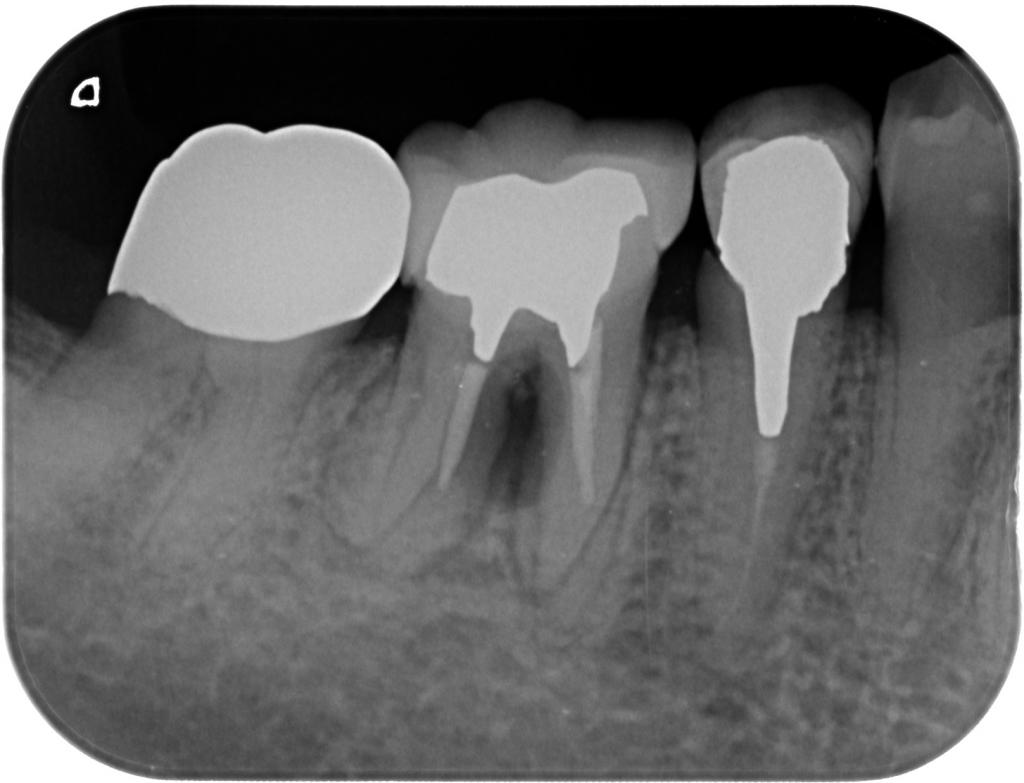

- その時のレントゲン写真です。

根尖部や根周囲では無く、分岐部の病変でした。

この様なケースでは治療をしても完治は困難なので、「根管治療を行ってみて、再度考えるか?」「抜歯をしてインプラントを行うか?」色々と相談し、抜歯しインプラントを行うことにしました。